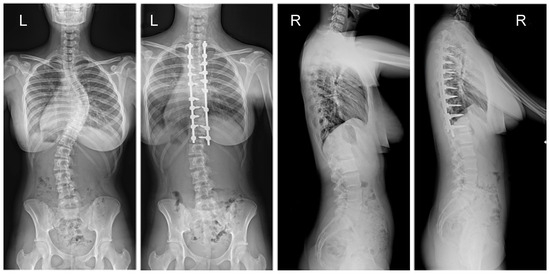

Figure 4.

X-rays of a 15-year-old girl with AIS, treated with smaller (standard) screw size of 5.5 and 2 titanium rods of 5.5 mm (G1). X-rays show curve before surgery and correction after surgical treatment.